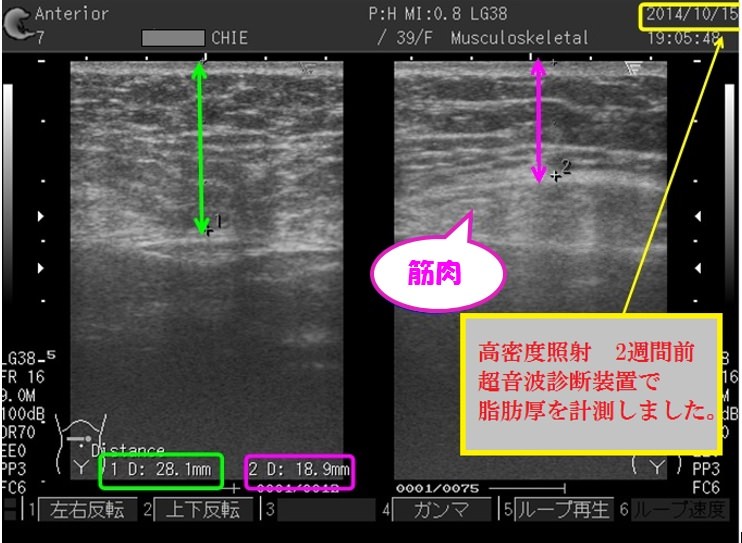

当院は医療用超音波診断装置を導入しており、施術の効果が見込める部分とそうでない部分を判断して、施術の精度を高めるよう努力しております。

超音波画像診断装置の解析イメージ

女性のお腹の部分の断面図です。

皮膚表面から筋膜までの皮下脂肪の厚みを調べます。

脂肪のセルライト化している部分も画像でわかります。